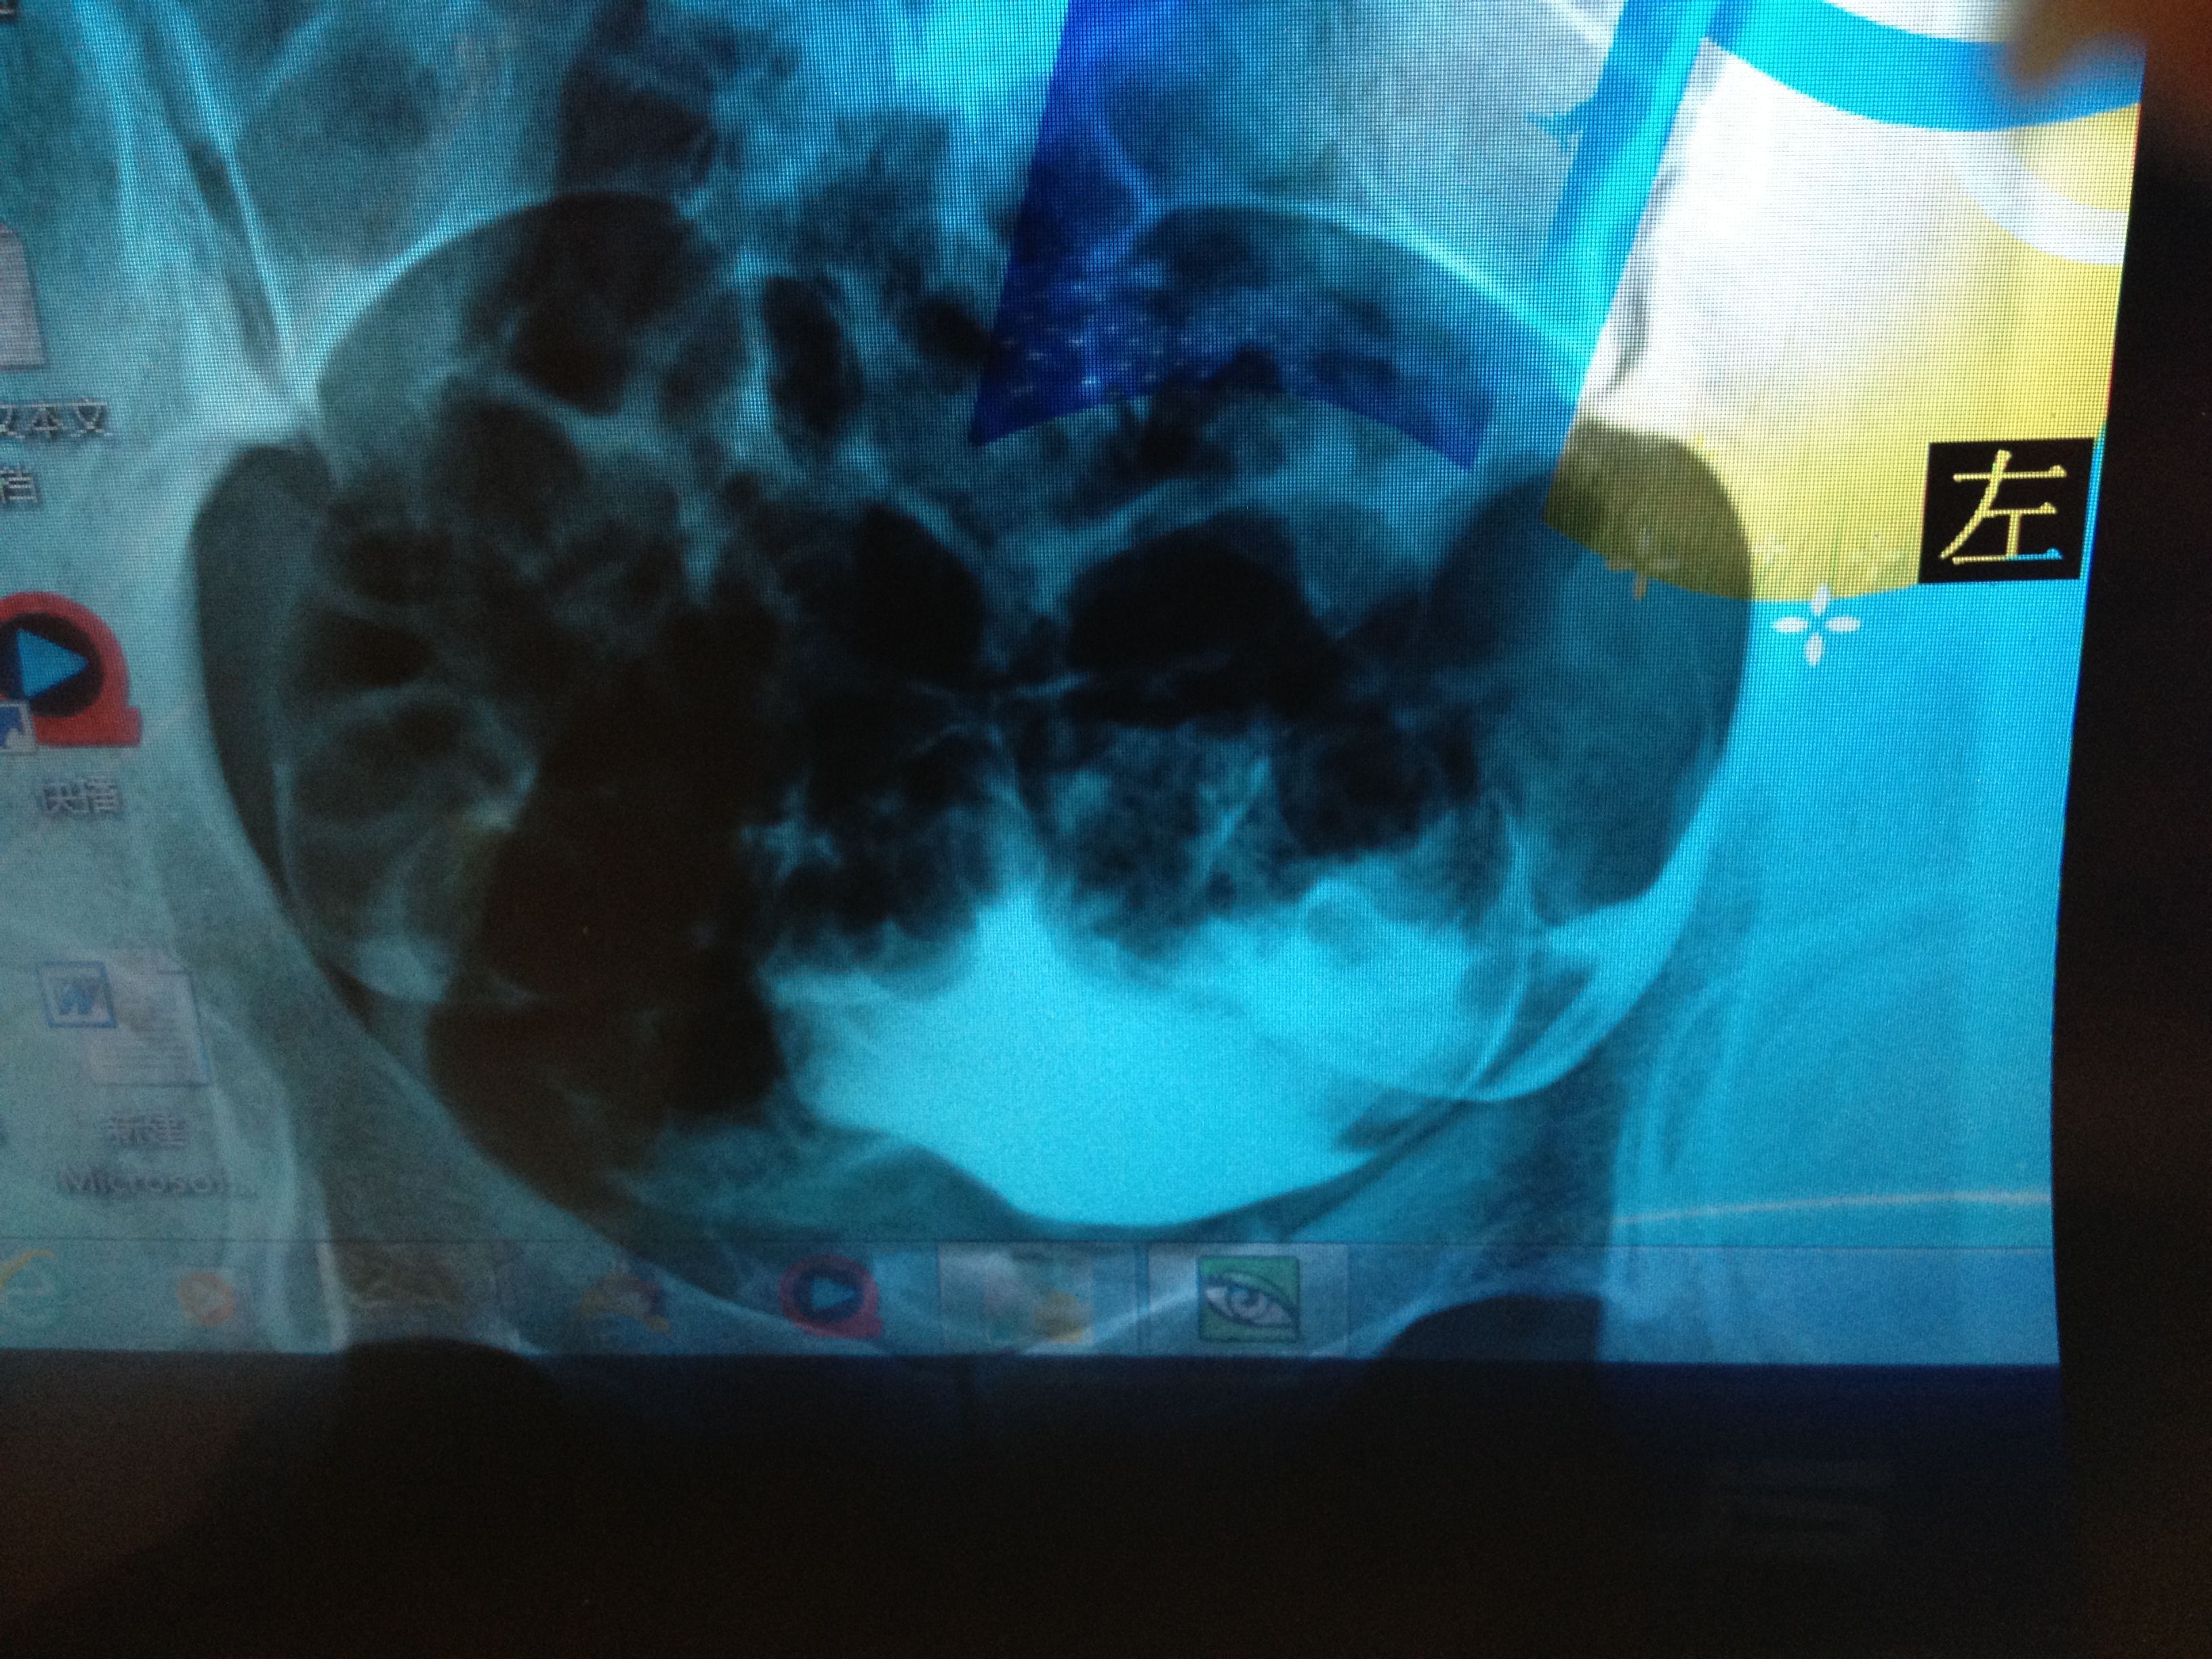

滑,并见部分照影剂自该侧伞端溢入盆腔,并见少许弥散。左侧输卵管大致 显影至壶腹区附近,进一步注入照影剂未见任何进展。第三张片于盆腔内可见散在片絮状及条弧状照影剂影,弥散尚可以。医生说右侧细,可能有炎症,左侧不通,两侧都得通水,我想问问有通水的必要吗?还有我的右侧是不是良好的?还是有炎症,还有偏细?应该怎么治疗?前两张是刚开始的,后两张是20分钟后的。还有现在拿到抗精子化验单有一项是阳性?怎么办?还有那个准吗?